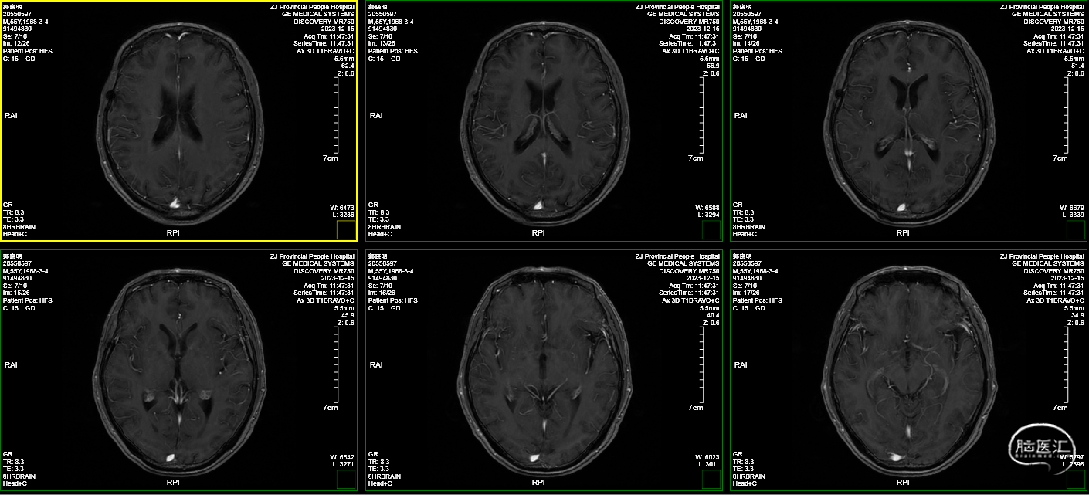

术后一年半

术后2年,患者一般状态良好,肿瘤未见复发,光动力瘢痕形成